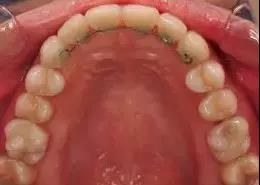

2、舌侧丝保持器:一般粘接于前牙的舌侧,起固定作用。由于舌侧丝很细,固定在牙齿内侧,可以和哈雷或隐形保持器一起佩戴。医生建议一般都是戴终生的。舌侧丝一般是戴在拆牙套之前的,上下前牙3到3,各粘6颗前牙,可以防止前牙发生移位。